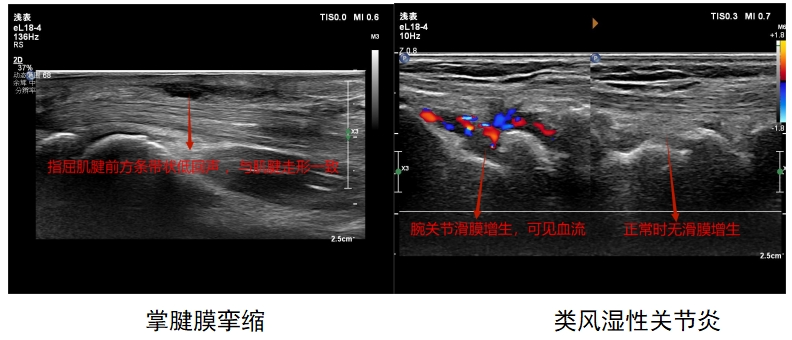

让我们一起看一下肌骨超声图像吧

7.手部超声检查:三角纤维软骨复合体TFCC损伤、腱鞘炎、指伸肌腱损伤、掌腱膜挛缩、腱鞘巨细胞瘤、腱鞘囊肿、血管球瘤、腱帽损伤并伸肌腱滑脱、钙化性关节周围炎、手异物等。

3.腕关节超声检查:腕管综合征、桡骨茎突狭窄性腱鞘炎(妈妈手)、扳机指、类风湿性关节炎、拇长屈肌腱断裂、前臂交叉综合征等。